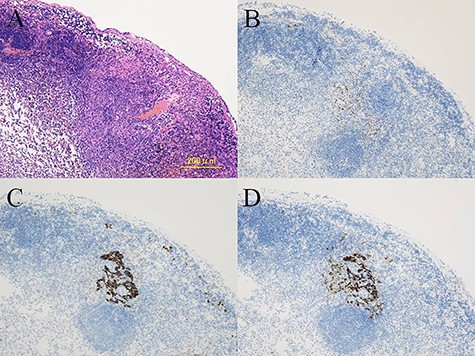

A 20-year-old man was referred to our hospital because of a tumor in his left lung that was discovered on chest radiographs. Chest computed tomography (CT) showed a 35-mm nodule in the lower lobe of the left lung (Fig. 1a). Fluorodeoxyglucose-positron emission tomography (FDG-PET) showed high accumulation in the nodule (maximum standard uptake value (SUVmax): 5.9; Fig. 1b). There was no accumulation in the hilar and mediastinal lymph nodes. Bronchoscopic examination and cryobiopsy were performed, which indicated suspicious for sclerosing pneumocytoma. To confirm the diagnosis and for treatment, we performed video-assisted thoracoscopic surgery (VATS). Intraoperative frozen pathological examination revealed that there were no metastases in the segmental lymph nodes (No. 13). Then, we performed basal segmentectomy considering curability and the preservation of pulmonary function. The operating time was 154 min and blood loss was 30 ml. However, the postoperative pathological diagnosis revealed lymph node metastasis in the segmental lymph nodes. Considering the possibility of remaining lymph node metastases, we performed additional resection of segment 6 (completion lower lobectomy) and hilar and mediastinal lymph node dissection by VATS, 2 weeks after the first surgery. The operating time was 266 min and blood loss was 200 ml. Hilar adhesions were moderate, and these were carefully dissected to avoid injuring the pulmonary artery. Then, the pulmonary artery was safely cut using a stapler. The bronchus of the left lower lobe was cut at the root using a stapler, followed by radical hilar lymph node dissection. The patient’s postoperative course was favorable, and he was discharged 13 days after the second surgery. Pathological examination of the second resected specimen revealed lymph node metastases in the interlobar (No. 11) and mediastinal lymph nodes (No. 4 L, 7 lymph nodes; Fig. 2). Six months after the surgery, he was alive without no recurrence or metastasis.

Histological findings showing the metastatic tumor in the mediastinal lymph nodes (A). Immunohistochemistry demonstrating positive staining for TTF-1 (B), AE1/AE3 (C), and EMA (D) in the metastatic tumor cells.